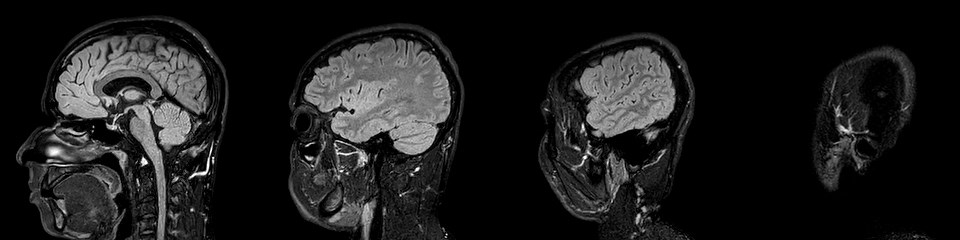

Córtex pré-frontal, ou mais precisamente córtex orbitofrontal, é o nome de uma das regiões do cérebro onde muitos cientistas procuram os possíveis sinais da confiança. Fica mesmo atrás dos nossos olhos. Aparentemente, essa é uma das zonas onde será possível observar os disparos dos nossos neurónios quando estão envolvidos numa decisão que tomamos com confiança. Mas, seguramente, não será a única. As imagens da ressonância magnética de Nelson Évora mostram um bonito cérebro a preto e branco, mas, para já, não nos dão pistas sobre a sua confiança. Resta-nos confiar nas suas palavras.

Zachary Mainen é um dos muitos investigadores que querem saber mais. Apesar dos avanços nas técnicas de imagens que nos permitem hoje espreitar para dentro dos nossos cérebros e decifrar coisas absolutamente incríveis, falta aprender muito. “No laboratório, em animais, observámos neurónios individuais, células individuais. Quando olhamos para uma ressonância magnética, olhamos para milhões de células ao mesmo tempo. Surpreendentemente, já é o suficiente para retirar informações fantásticas. Somos, por exemplo, capazes de dizer, olhando imagens e analisando dados, em que é que alguém está a pensar. Um objecto. Isso já é possível. Somos constantemente surpreendidos com o que se consegue fazer com estas técnicas. Embora a informação seja ainda muito crua, os métodos de análise são hoje muito sofisticados e rápidos”, constata.

Isso quer dizer que um dia seremos capazes de dizer de forma definitiva onde mora a confiança no cérebro? Seremos capazes de um dia olhar para um cérebro e dizer: "Esta pessoa é confiante"? “É possível. Não é impossível. Não conseguimos fazer isso agora. Provavelmente, não será nada tão simples como algo que se possa ver pelo tamanho de uma região, mas, repito, é impressionante o que conseguimos ver. Principalmente, quando sabemos de que é que estamos à procura e quando concebemos um estudo de forma adequada”, arrisca Zachary. E remata: “Não posso fazer esse anúncio neste momento, mas provavelmente vai acontecer. O cérebro é um mar gigantesco.” Ou um universo, diz Nelson Évora.